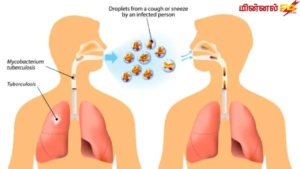

- விழிப்புணர்வு: காசநோய் என்பது ஒரு பரவலான தொற்று நோயாகும். இதன் தாக்கங்கள் மற்றும் தடுப்பு முறைகளை பற்றி மக்களுக்கு அறிவுறுத்துதல் முக்கியம்.

- இருமல் அல்லது தும்மல் செய்யும் போது வாயை மூடுதல்.

- தூய்மையான சுற்றுச்சூழல்: காற்றோட்டமான மற்றும் சுத்தமான இடங்களில் வாழ்வது காசநோய் பரவலை குறைக்க உதவும்.